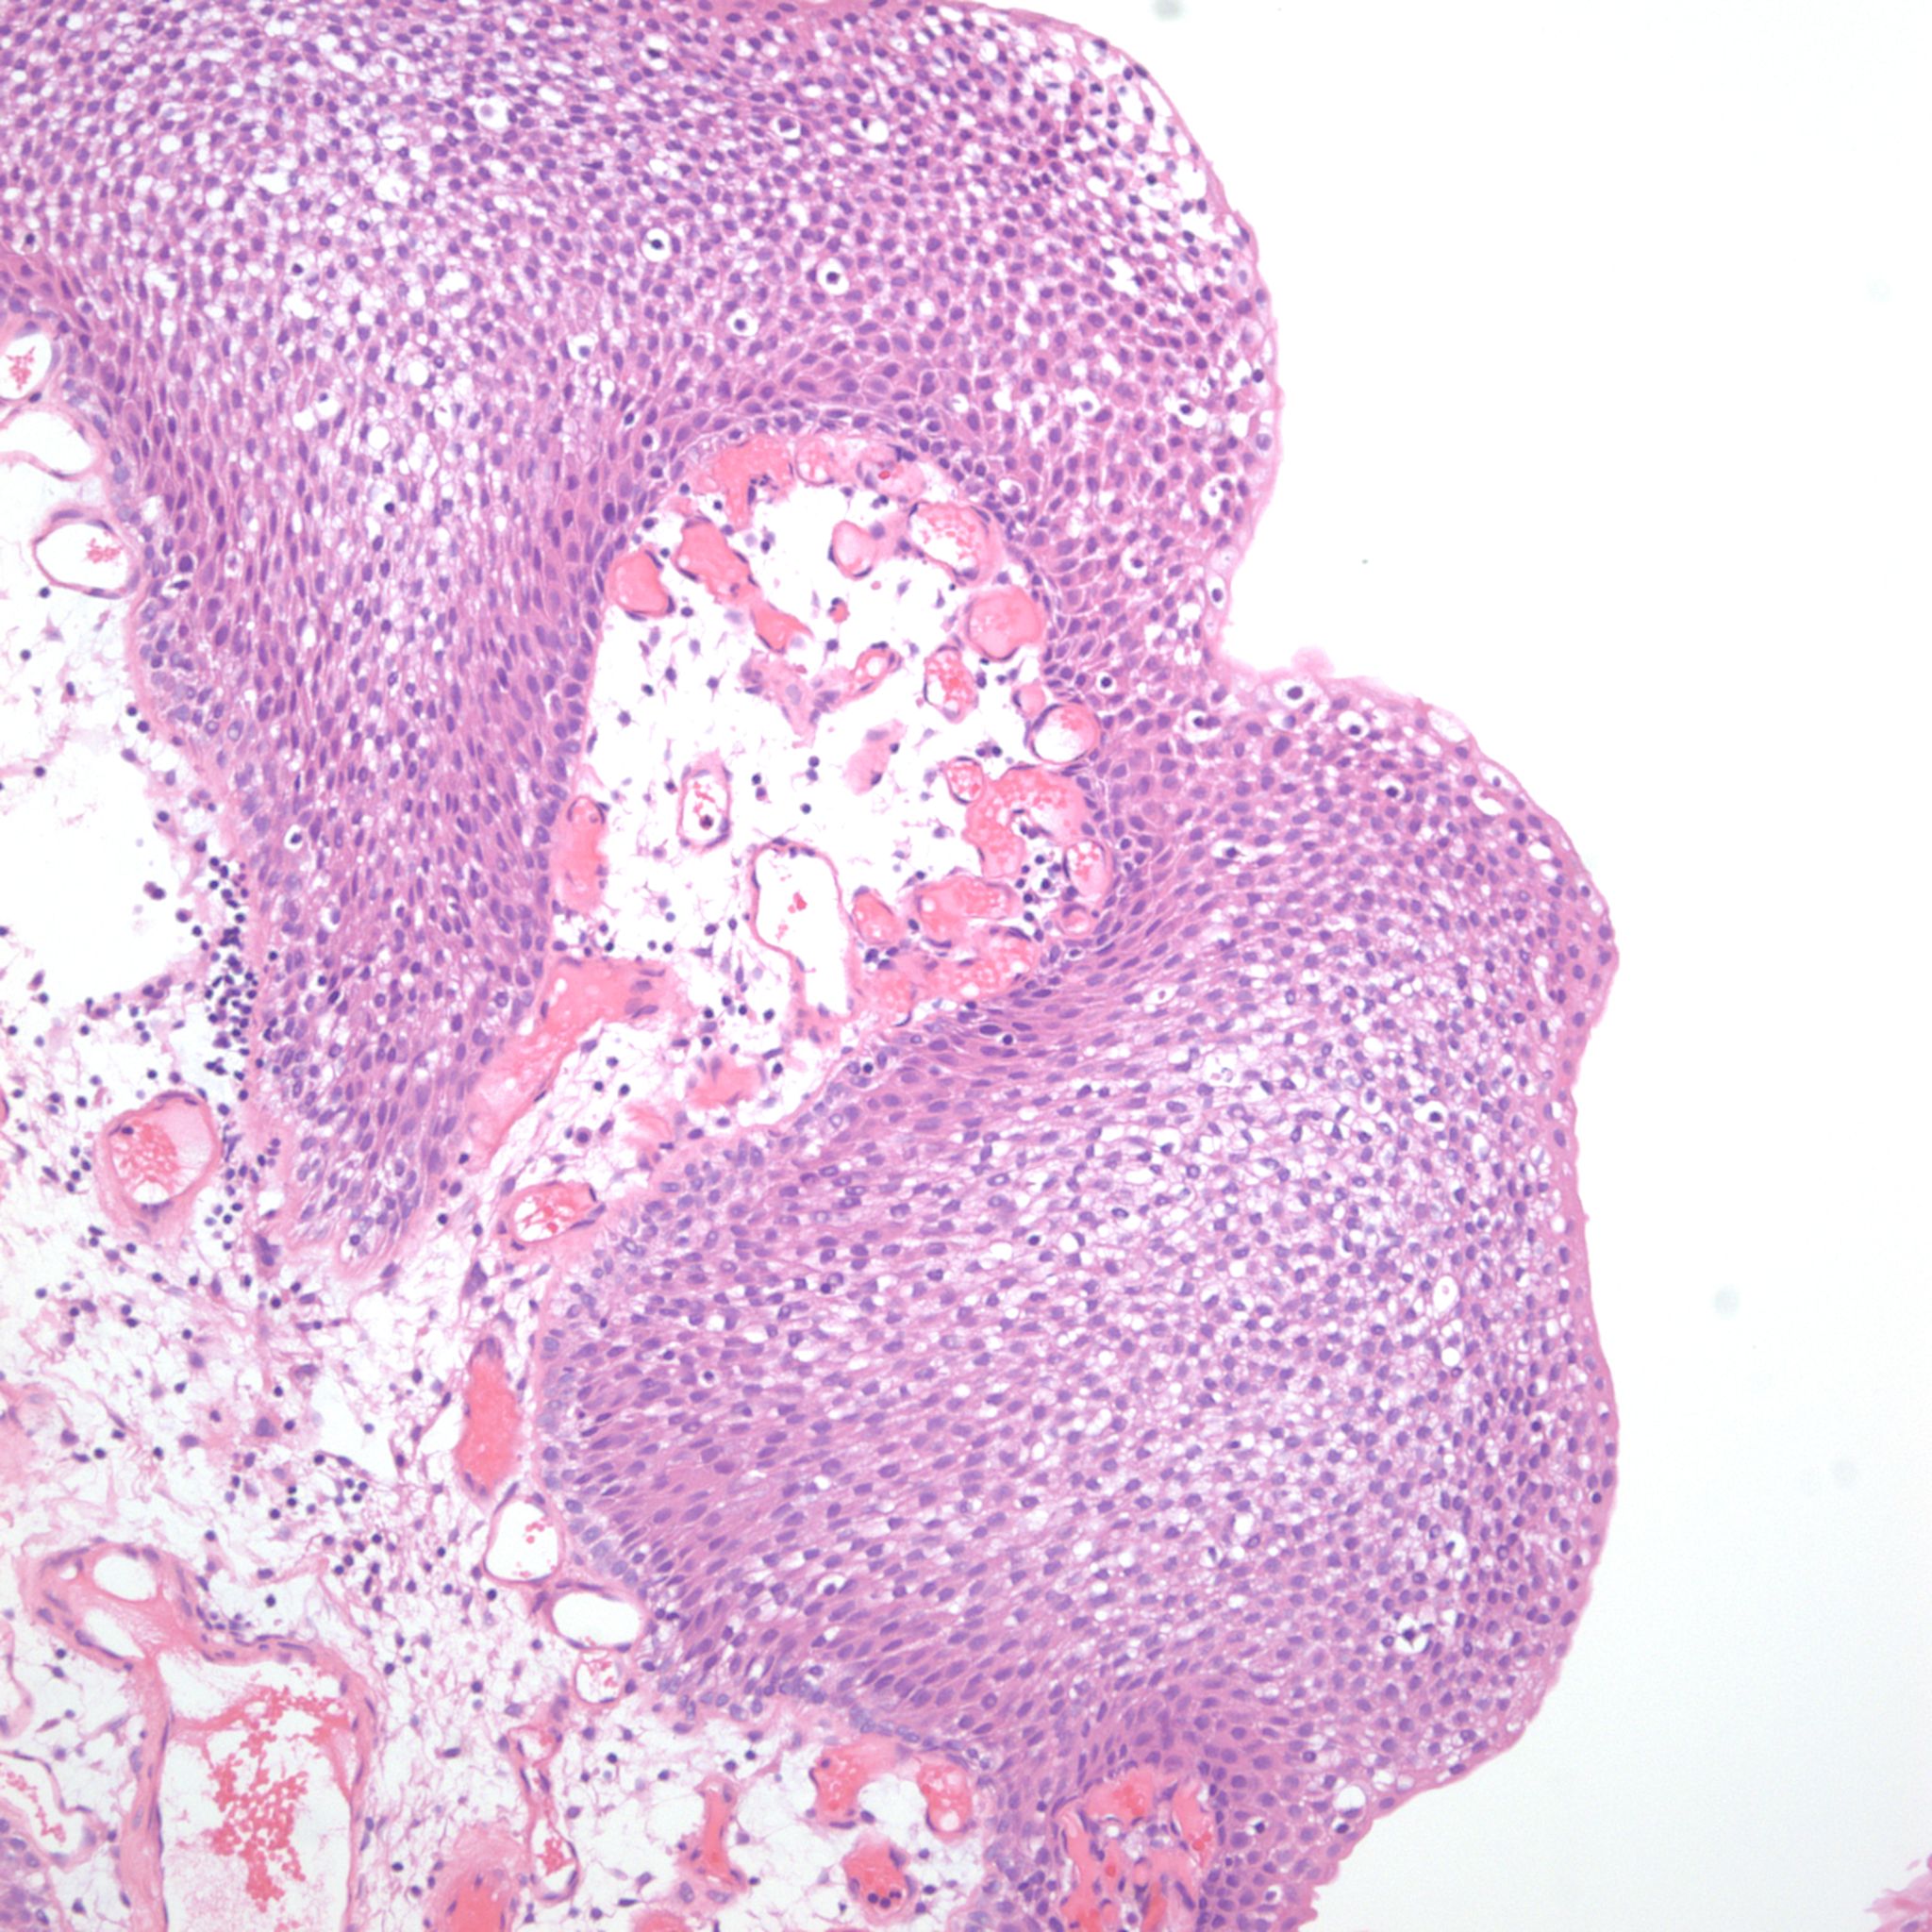

Bladder Papillary Lesions

Case ID: 315